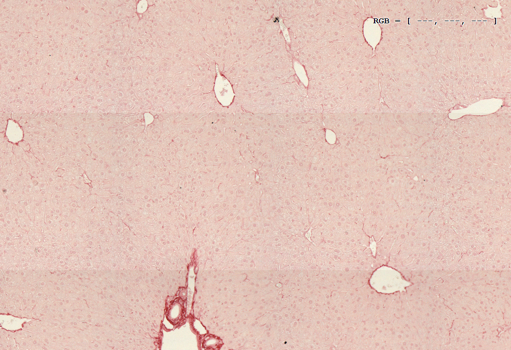

Sometimes humans having obesity and fatty liver develop fibrosis, which is a wound healing process that has gone awry and results in detrimental scarring of organs and their dysfunction. To measure fibrosis levels in our mice, we perform Sirius red staining of liver sections depicted in the picture below. On the left-hand side is a non-fibrotic liver from lean mice and on the right side is a fibrotic liver of obese mice.